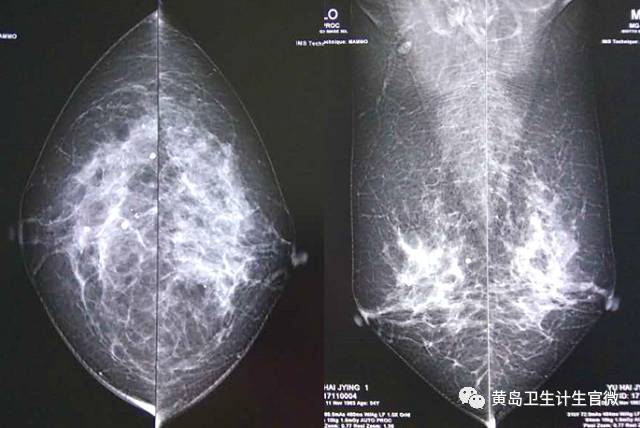

2017年11月20日,青岛西海岸新区妇幼保健计划生育服务二中心新购置世界专业乳腺摄影设备的代表--意大利Gitto全视野数字X线乳腺摄影系统(DR),正式投入使用!

该设备采用目前先进的数字平板直接成像技术,成片速度的加快缩短了检查时间,更大大降低放射剂量,使体检普查过程更加安全放心。数字X线乳腺机与传统CR乳腺机相比,具有无可比拟的图像清晰度及高对比度的优势。其通过配合不同的压迫板以适应不同大小的女性乳房检查,再结合处理工作站以及乳腺专用5兆双屏显示屏,可显示良性、恶性、不定性的微小钙化,最小尺寸为20um,其中,对于典型恶性,如细小线样、分枝状、多形性、蠕虫样钙化可直接判读BI-RADS 5类,对乳腺疾病的诊断能力有极大提升,可最大限度地做到早发现、早诊断、早治疗。

青岛西海岸新区妇幼保健计划生育服务二中心开展乳腺癌X线筛查工作10余年来,积累了丰富的临床经验,为近2万名服务对象提供了乳腺癌筛查服务。其中确诊近200人,均已指导其及时治疗,有效防止了疾病恶变。此次新设备的投入使用,对进一步提升乳腺X线诊断能力,提高乳腺疾病诊断水平、降低乳腺癌致死率均具有重要意义。